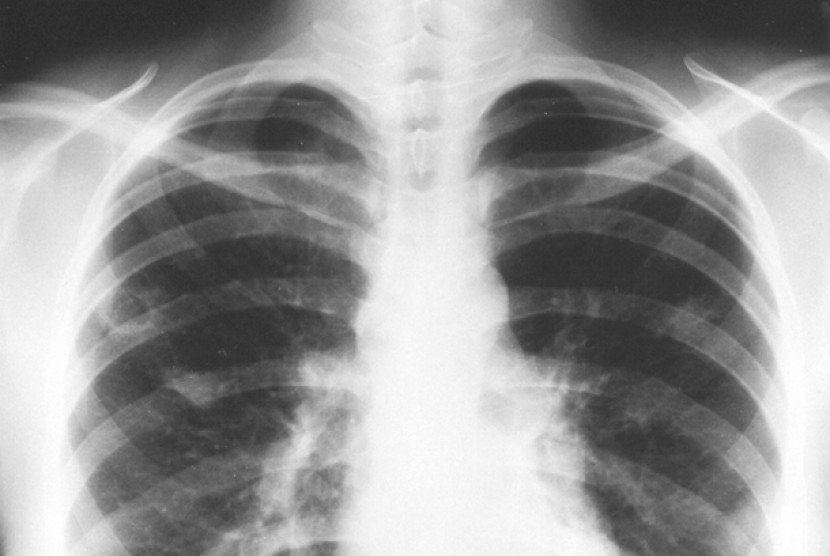

Flek paru paru adalah istilah awam yang digunakan untuk menyebut adanya bercak, bayangan, atau noda yang tampak tidak normal pada hasil foto rontgen (X-ray) dada, khususnya di area paru-paru. Dalam bahasa medis, dokter biasanya tidak menyebutnya sebagai “flek”, melainkan menggunakan istilah seperti lesi, infiltrat, nodul, fibrosis, atau istilah radiologis lain sesuai bentuk dan karakter gambaran yang terlihat.

Secara sederhana, flek paru paru bukanlah nama suatu penyakit, melainkan temuan pada pemeriksaan radiologi yang menunjukkan bahwa ada sesuatu di jaringan paru yang tampil berbeda dari paru normal. Bercak ini bisa tampak sebagai area yang lebih putih, lebih padat, mengabur, atau penebalan tertentu dibandingkan jaringan paru di sekitarnya. Karena itu, istilah “flek” lebih menggambarkan bentuk gambaran pada rontgen.

Ringkasnya, flek paru paru adalah istilah umum untuk setiap bercak atau bayangan tidak normal yang tampak pada foto rontgen paru, dan bukan diagnosis akhir suatu penyakit. Istilah ini menjadi “tanda awal” yang kemudian perlu dijelaskan lebih lanjut oleh tenaga kesehatan untuk mengetahui apa makna sebenarnya dari gambaran tersebut pada masing-masing pasien.